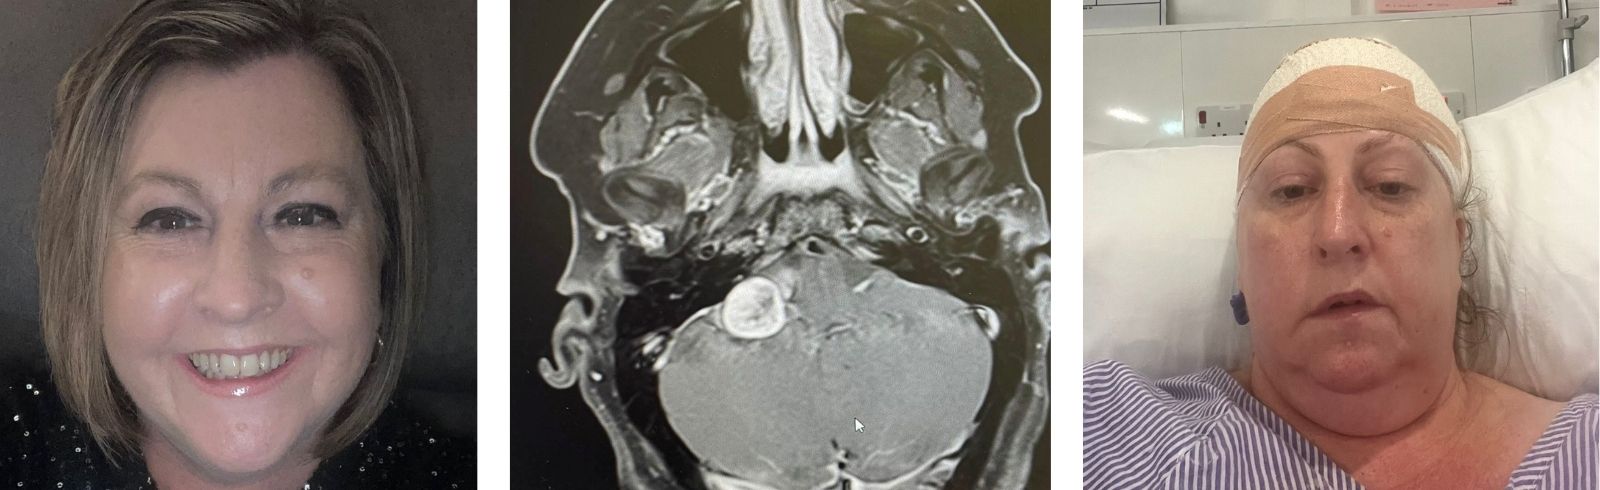

As the leading voice of the brain tumour community, we bring news from across the worlds of research, campaigning and fundraising. Read the latest brain tumour stories and news here.